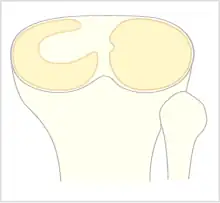

Le ménisque normal a une forme de croissant fin. Dans le cas du ménisque discoïde il existe un épaississement du ménisque pouvant aller d'une forme en croissant épais jusqu'à une forme de disque recouvrant le plateau tibial.

La classification de Watanabe décrit trois types de ménisque discoïde selon le degré de couverture du plateau tibial et selon l'attache postérieure du ménisque : ménisque discoïde complet, incomplet et variant-ligament de Wrisberg[1],[2].

Le ménisque discoïde complet recouvre totalement le plateau tibial externe (type I)[2]. Le ménisque discoïde incomplet (type II) ne le recouvre qu'incomplètement[2]. Dans le cas du variant-ligament de Wrisberg, il n'existe pas de frein méniscal postérieur[2].